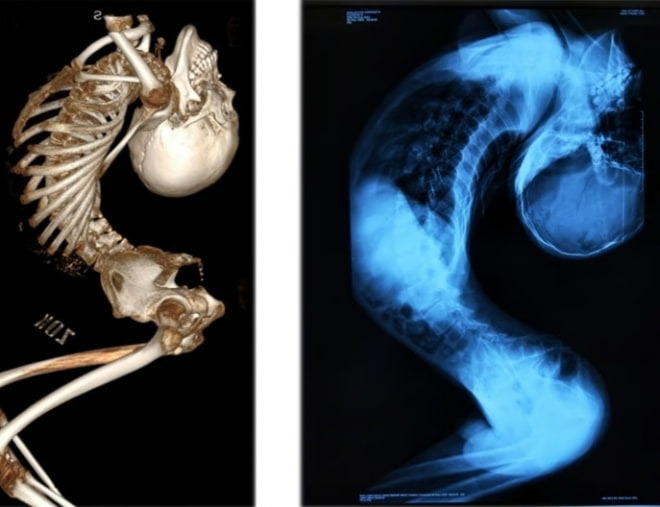

폴더 소년의 치료는 매우 복잡했습니다. 초기에는 약물 치료와 물리 치료가 주로 이루어졌습니다. 염증을 줄이고 통증을 완화하기 위한 다양한 약물이 사용되었고, 물리 치료를 통해 근육을 강화하고 유연성을 높이기 위한 노력이 있었습니다. 그러나 이러한 방법만으로는 한계가 있었고, 결국 대수술이 필요하다는 결론에 이르게 되었습니다.